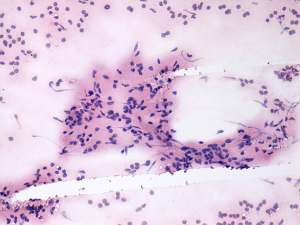

Cytology was performed and resulted in thyroiditis. There were scattered number of lymphocytes and multinucleated giant cells were also found.

The presence of multinucleated giant cells composed of epithelioid cells resembles that observed in de Quervain's thyroiditis. This type of multinucleated cells occurs rarely in autoimmune thyroiditis.